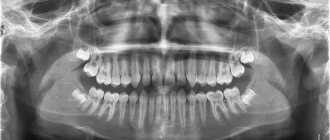

• X-ray diagnostics . Allows you to identify in detail even small defects on the root and determine the degree of caries damage. Most often, bite-wing radiographs and orthopantomograms are used for this.

Photo: caries inside a tooth root on an x-ray

It is difficult to independently diagnose root caries, and in some cases impossible. That is why you should not neglect a routine visit to the dentist, who can detect pathology at an early stage.